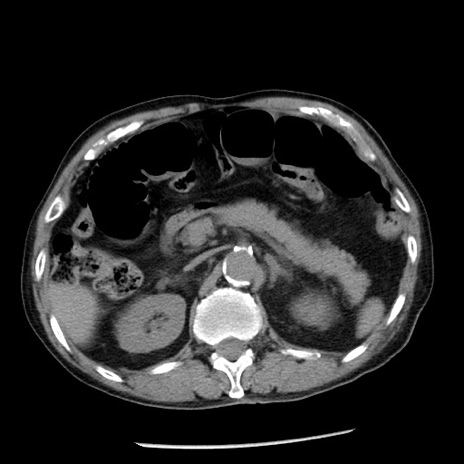

症例26(横断像)

【症例】80歳代男性

【主訴】嘔吐

【現病歴】昨晩2回嘔吐あり、今朝になっても嘔吐あり。来院。

【既往歴】胃潰瘍

【身体所見】意識清明、BT 37.6℃、BP 166/95mmHg、HR 100bpm、SpO2 97%、腹部:平坦・軟、腸蠕動音聴取良好、圧痛なし。

【データ】WBC 21900、CRP 1.46